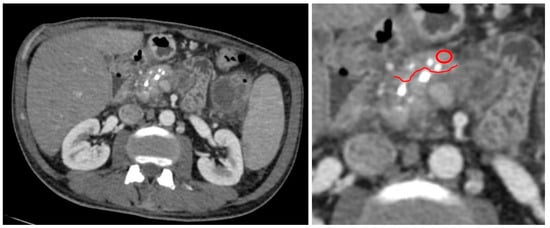

2.2. MDCT Examination

2.3. MDCT Result Post-Processing